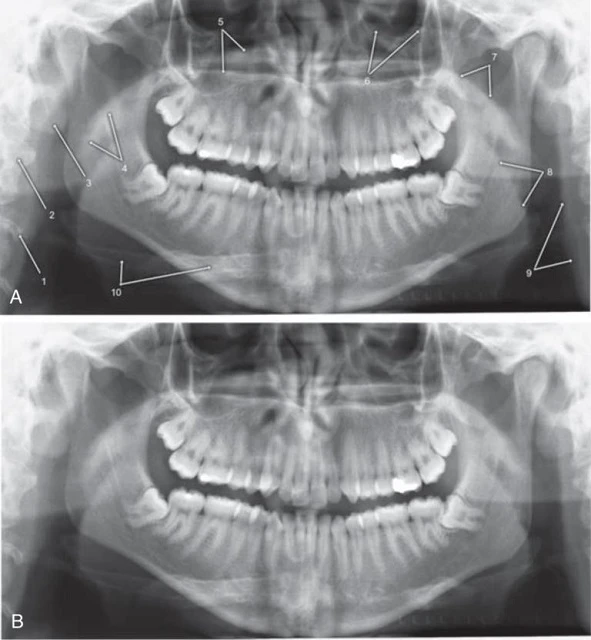

Hình 18. Những cấu trúc giải phẫu đốt sống, cổ và mô mềm trên phim x-quang toàn cảnh. Hình ảnh A (có ghi chú) và B (không ghi chú) trùng nhau của cùng một bệnh nhân. 1, Schmorl’s Node (biến thể giải phẫu bình thường của thân đốt sống). 2, Đốt sống cổ. 3, Thuỳ tai. 4, Khẩu cái mềm và lưỡi gà. 5, Khẩu cái cứng (đường phía dưới là chỗ nối giữa khẩu cái cứng và thành bên của xoang mũi bên phía receptor). 6, Vành ổ mắt. 7, Sàn vòm họng (mặt trên khẩu cái mềm). 8, Mặt sau của lưỡi. 9, Thành sau họng. 10, Xương móng.